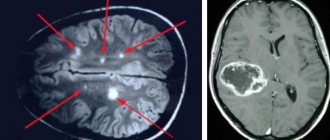

Metastases and brain tumor on MRI

What does MRI of the brain show, indications and contraindications, how to prepare

Among neuroimaging diagnostic methods, electromagnetic screening has the highest level of information content and reliability. MRI